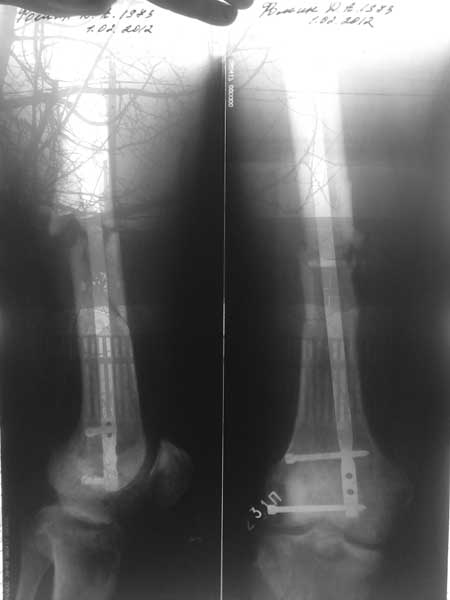

Не фотографируйте снимки на фоне заоконных пейзажей. Надо либо на фоне негатоскопа, либо хотя бы монитора с белым экраном на максимальной яркости.

И, еще раз, надо снимок на всем протяжении бедра, как уже сказано выше - и сколенным, и с тазобедренным суставами. Без снимка не догадаться, где заканчивается вверху стержень, где располагаются какие винты.